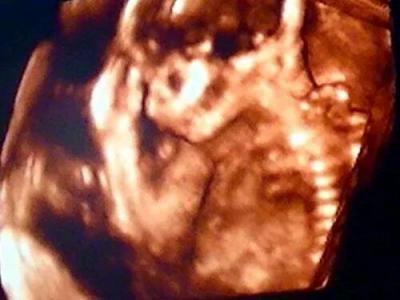

Das ist immer gemein ne....?!?! Wenn kejne Antwort auf einem Beitrag ist.Aber mach dir kejne Sorgen süße....manchmal übersehen das alle...und wenn dann noch neue einträge kommen ist es "Aus den Augen,aus dem Sinn" Das Bild ist aber super.Und man kann den kleinen Bauchbewohner super sehen.Siegt süß aus...als ob dein baby sich richtig in Szene gezetzt hätte...die Hand so leicht an den Kopf :-) Richtig schön

Ich bin eigentlich nicht so ein Fan von den 3D-Bildern, aber das gefällt mir wirklich!

Huhu, ich hatte heute auch 3D Termin und mein Bauchbewohner hat dauernd die Hände vor das Gesicht gehalten. Sah so ähnlich aus ;-) Aber sieht toll aus, Dein Bild! liebe Grüße Britta

Ich find 3D Bilder irgendwie etwas unheimlich... Aber schön, dass es dem Baby gut geht :)